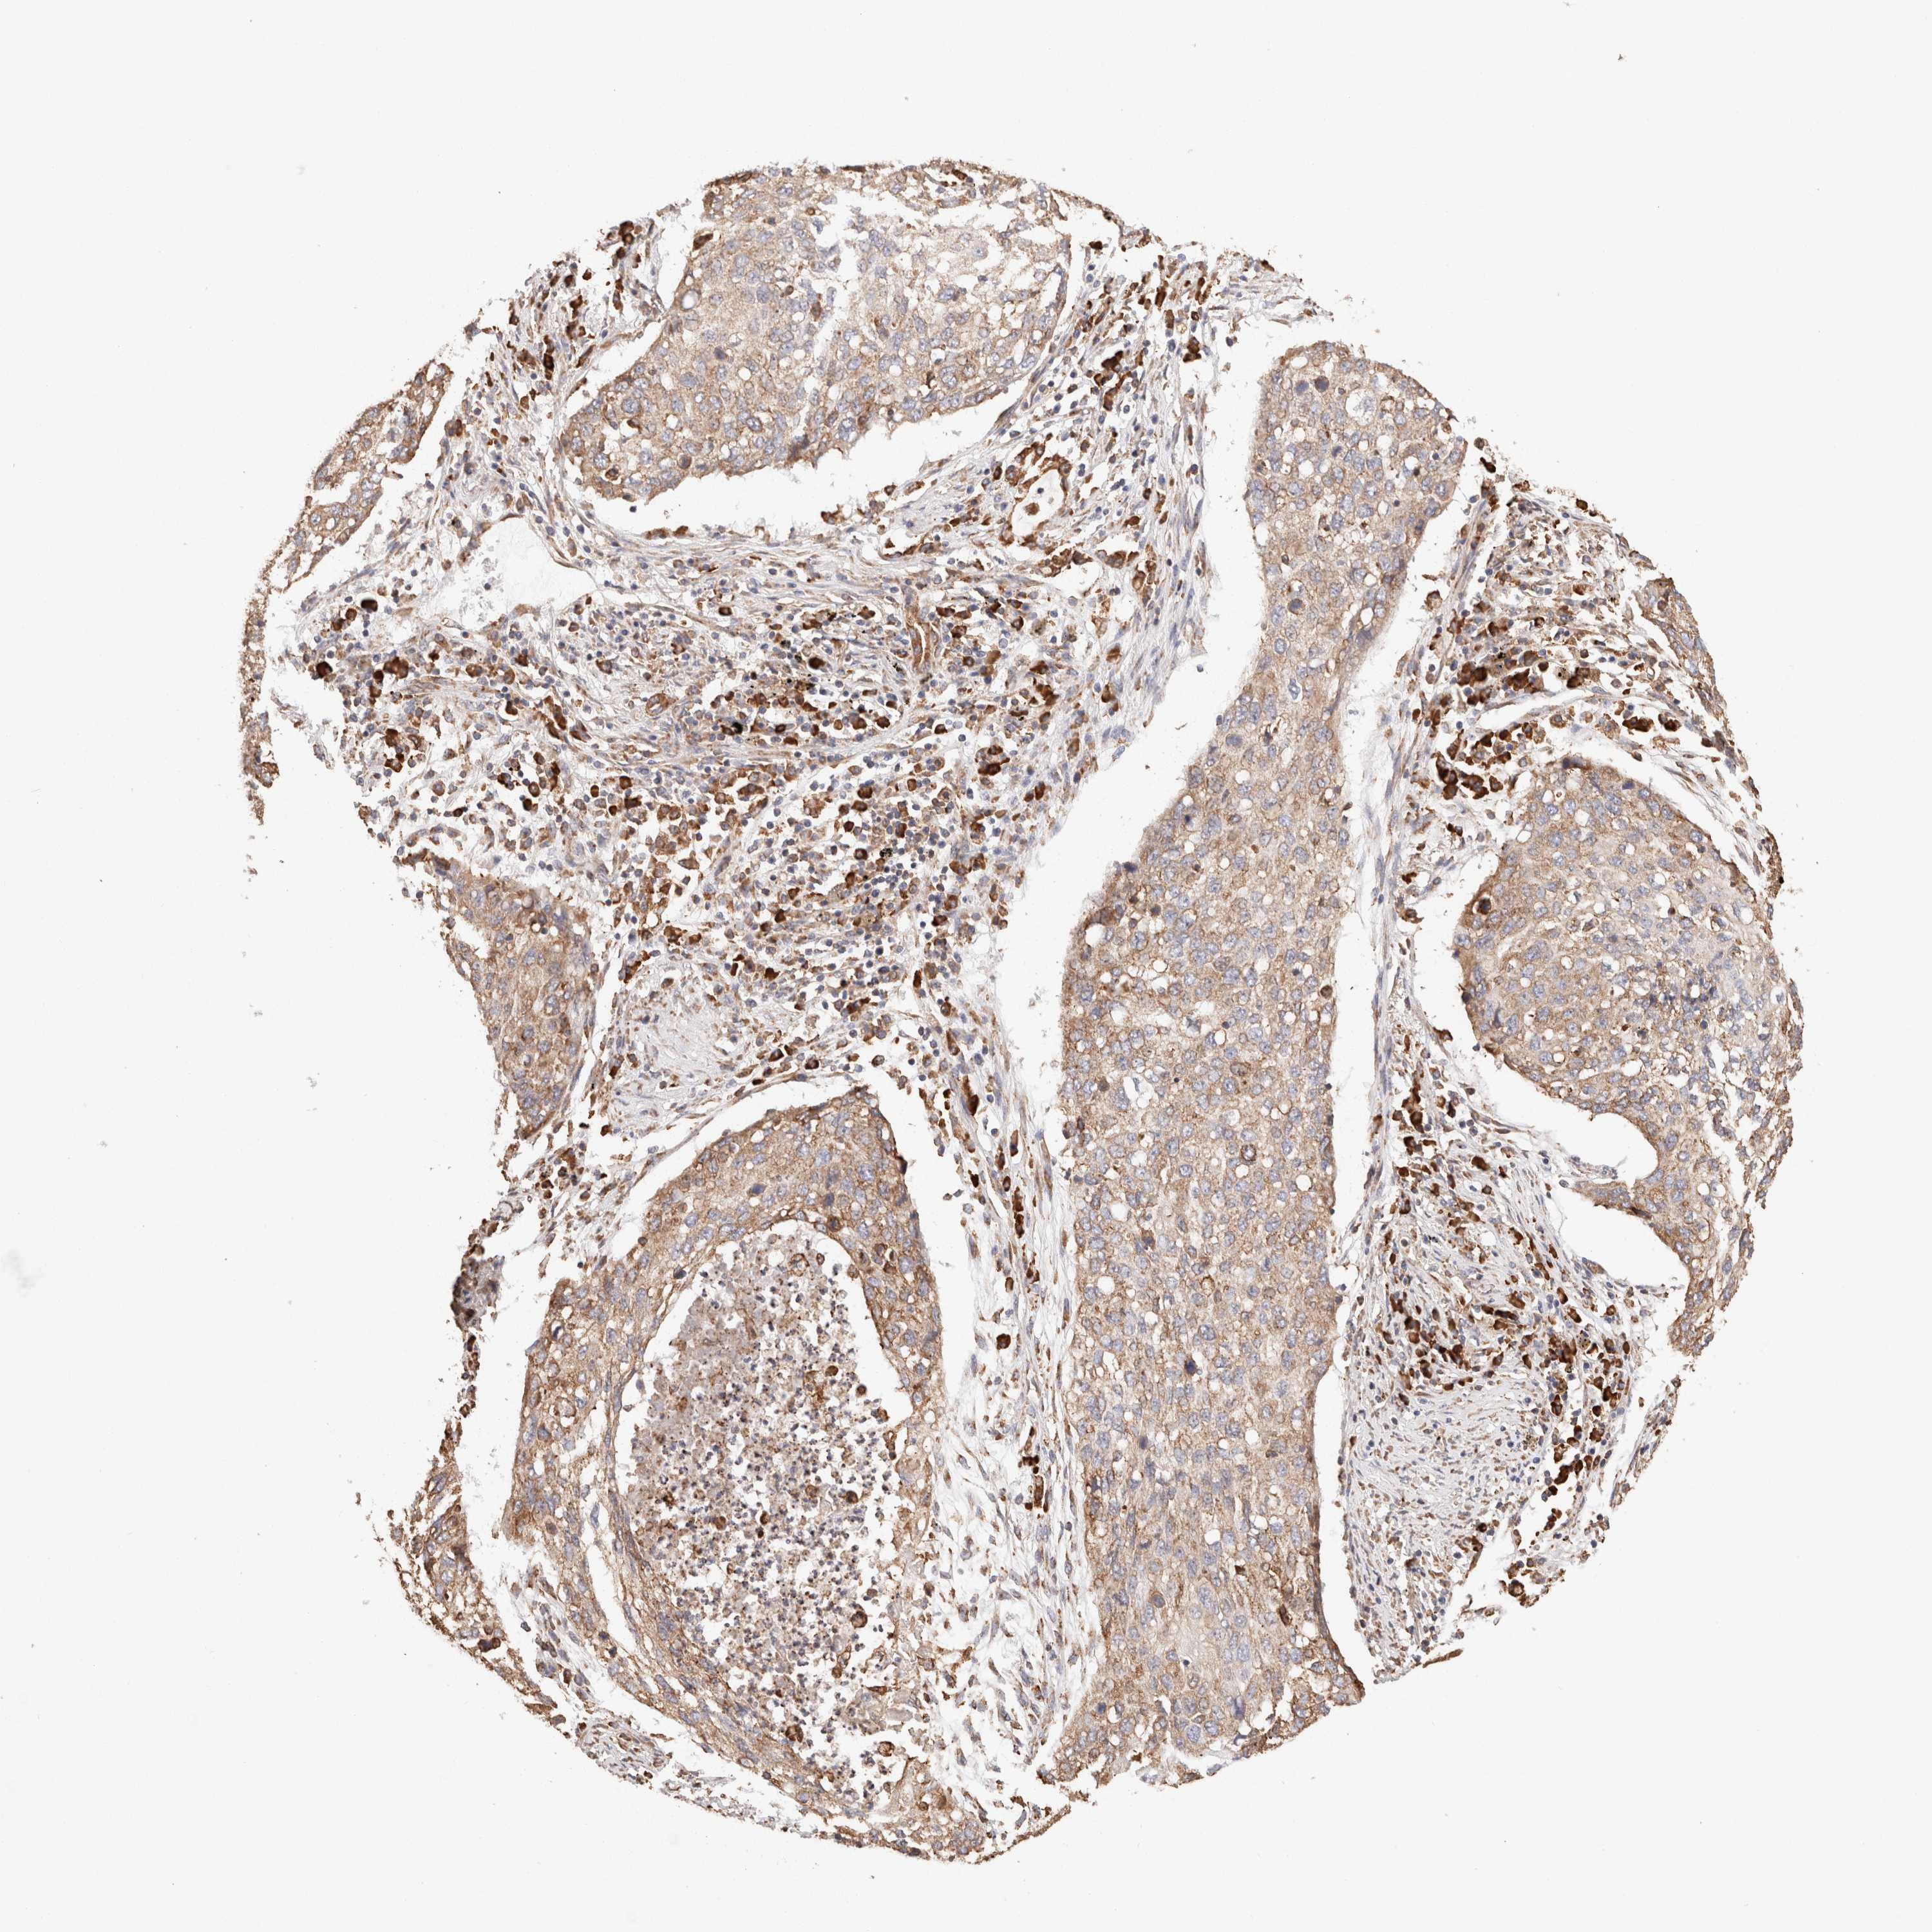

CANCER LUNG CANCER Show tissue menu

LUAD TCGA LUAD VALIDATION LUSC TCGA LUSC VALIDATION PROTEIN LUAD CPTAC PROTEIN LUSC CPTAC PROTEIN EXPRESSION

ANTIBODIES

AND

VALIDATION